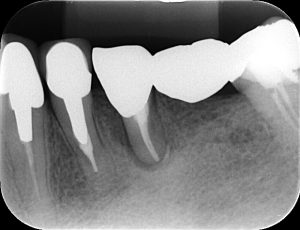

以前根管治療を受けた歯の周りの歯茎が腫れて来院された患者様です。

レントゲンで確認しました。

以前 今回

以前のレントゲンと比べ、今回のでは隣の歯との間が黒く見えます。

この部分の骨がなくなっている状態です。

その他の検査も行い、歯が割れていることが原因と説明し、残念ながら抜歯することになりました。